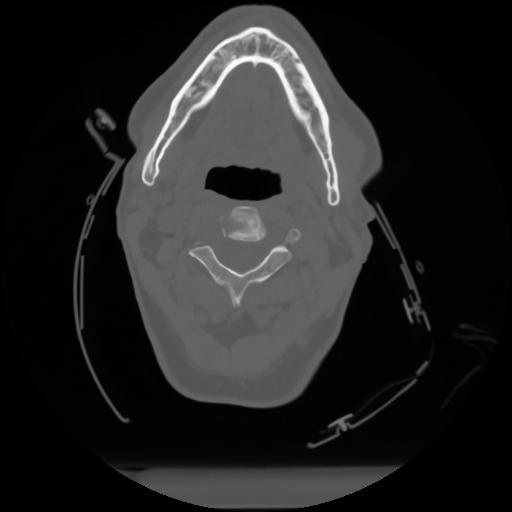

10 P.BLANDAS,,Axial,2.0,P.BLANDAS,,